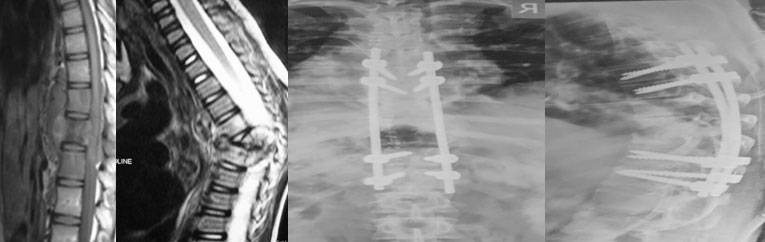

Some of the spinal corrections: